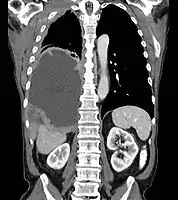

< Radiation Oncology < Mesothelioma

Mesothelioma Overview